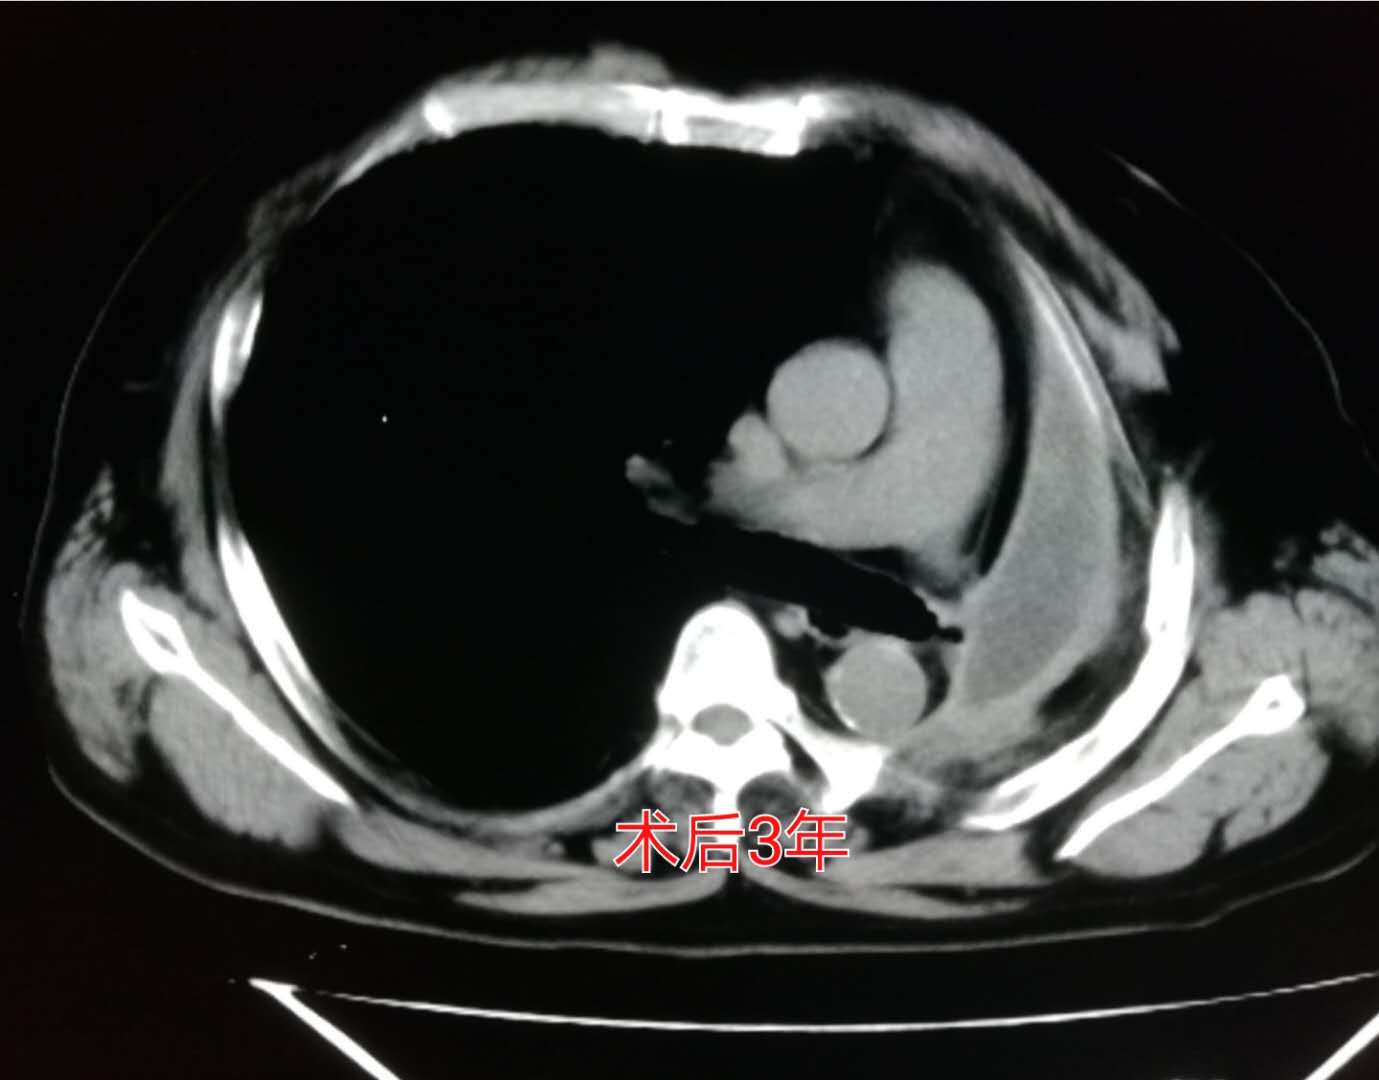

术后第3年复查的时候:

我们可以看到左侧胸腔形成了术后残腔。